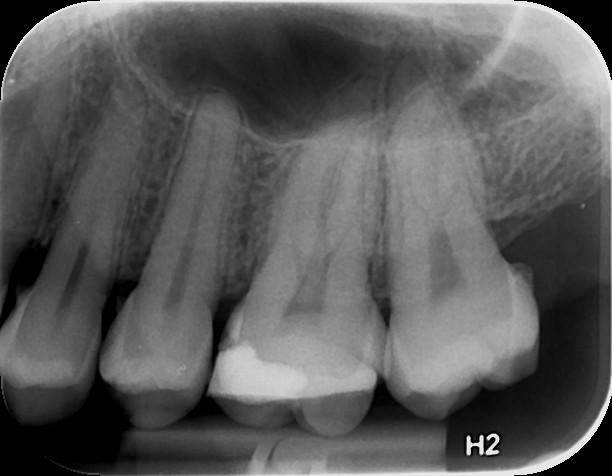

Με την οπισθομυλική ακτινογραφία επιτυγχάνεται η ταυτόχρονη απεικόνιση των μυλών των άνω και κάτω οπισθίων δοντιών ενός ημιμορίου (μιας πλευράς) με μία λήψη. Λαμβάνεται με την τοποθέτηση του ακτινογραφικού πλακιδίου εσωτερικά των δοντιών (προς την πλευρά της γλώσσας και του ουρανίσκου) και παράλληλα με αυτά. Χρησιμοποιείται ειδικός συγκρατητήρας οπισθομυλικών, τον οποίο δαγκώνει ο εξεταζόμενος.

Χρησιμοποιείται για την ανίχνευση τερηδόνων στις μύλες των δοντιών, κυρίως στις όμορες επιφάνειές τους (γειτνιάζουσες επιφάνειες δοντιών).

Η λήψη της είναι γρήγορη (διαρκεί λίγα δευτερόλεπτα) και ανώδυνη.